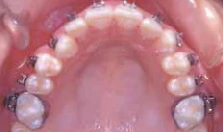

Hình 11a Một ví dụ lâm sàng của gắn mắc cài xoay. Điều chỉnh hoàn toàn sự xoay có thể đạt được trong giai đoạn sớm của điều trị mà không cần thêm phương pháp đặt biệt nào khác. Xem thêm Hình 11b.

Hình 11b